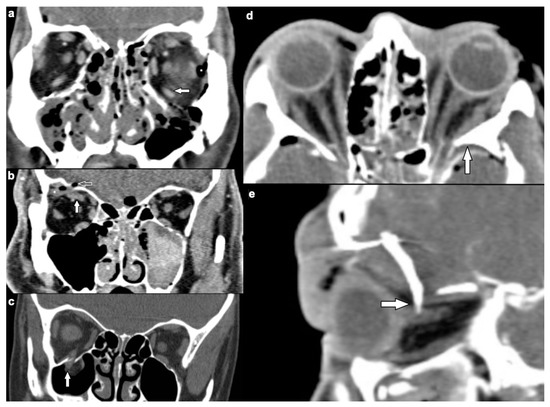

| Extraocular muscles | 54 (53.5) | |

| dislocation | 45 (44.6) | |

| pierced by bone fragment | 8 (7.9) | |

| intramuscular foreign body | 1 (1.0) | |

| Optic nerve | 24 (23.8) | |

| elongation | 13 (12.9) | |

| otherwise altered morphology | 10 (9.9) | |

| pierced by foreign body | 1 (1.0) | |